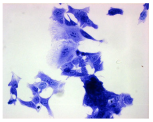

| Control | Doxycycline (DOX) | DOX + C1 | DOX + C2 | |

|---|---|---|---|---|

| SH-SY5Y cells | ||||

| May–Grunwald staining | ![]() | ![]() | ![]() | ![]() |

| HepG2 cells | ||||

| HEK-293 cells | ||||